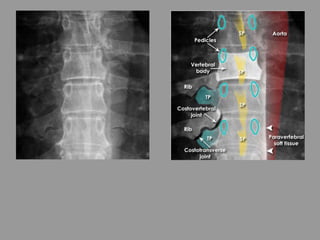

Thoracic spine - Systematic approach

• Alignment - The vertebral bodies and spinous processes

(SP) are aligned

• Bones - The vertebral bodies and pedicles are intact

• Other visible bony structures include the transverse

processes (TP), ribs, and the costovertebral and

costotransverse joints

• Spacing - Each disc space is of equal height when

comparing left with right. The pedicles gradually become

wider apart from superior to inferior

• Soft tissue - Note the normal paravertebral soft tissue

which forms a straight line on the left - distinct from the

aorta